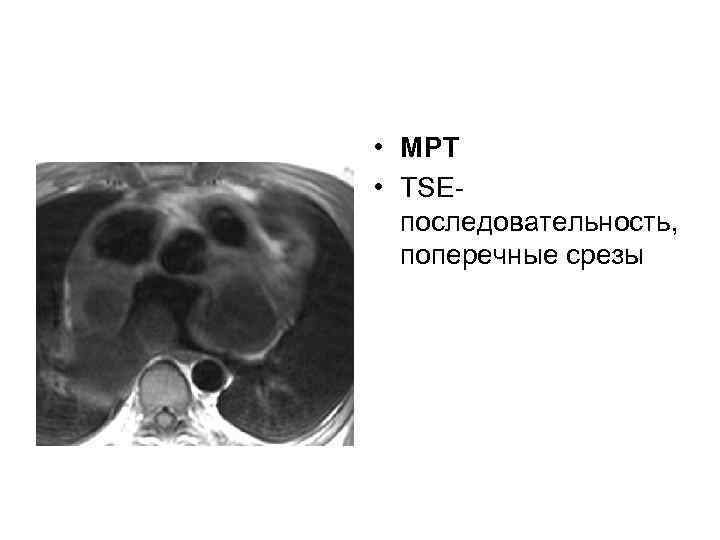

• МРТ • TSEпоследовательность, поперечные срезы